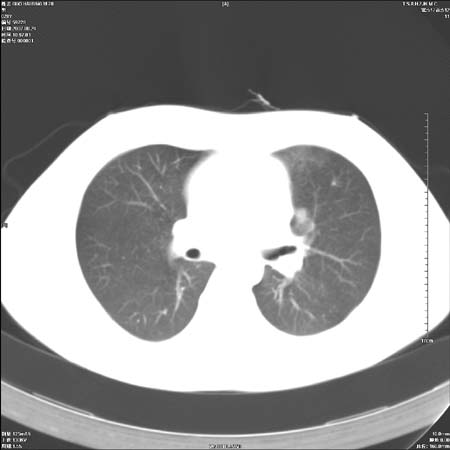

首先这个病例应该加薄层面扫描-可以很好显示支气管与肿块的情况。

本例倾向周围型肺癌

鉴别:中央型肺癌-肿块那么明显一般合并节段肺不张或阻塞性炎症。

本例肿块边缘外侧可见左上叶各段支气管。

左侧肺门区见一块状病灶可见分叶,纵隔内及左肺门见肿大淋巴结,应该是周围型肺癌而不是中心型肺癌,原因有以下2点,1未见阻塞肺气肿和阻塞性炎症,这么大肿块如果是中心型肺癌就是未分化型或小细胞型肺癌不出现阻塞性肺不张也应该有阻塞炎症或阻塞性肺气肿,2如果是中心型肺癌临床出现最早的症状是咳嗽(此时可无任何异常影象),而此人这么大肿块只有背部隐痛是体检才发现无法解释.

左肺门区分叶状软组织肿块,纵隔内有肿大淋巴结,诊断肺癌应该问题不大。